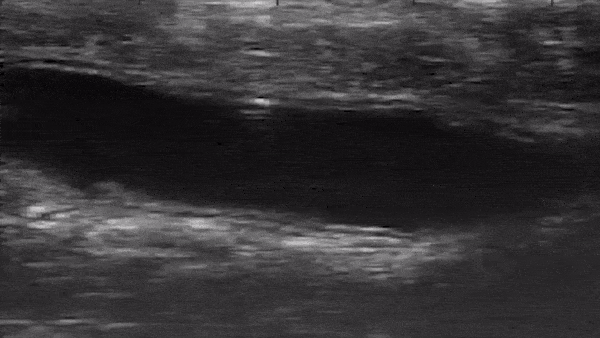

研究チームは、この極小ロボットを直腸から挿入し、麻酔下にある生きたマウスの結腸で生体内実験を実施。超音波装置を用いて、この極小ロボットが結腸の内部で移動する様子をリアルタイムで観察した。

結腸では、液体や固体が一方向に移動するのに対して、ロボットは逆方向に移動しなければならない。この実験では、この極小ロボットが後方転回しながら起伏の激しい結腸の内部を難なく移動する様子がとらえられている。